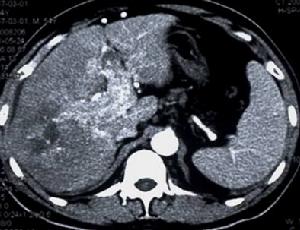

2.微粒栓塞治療巨塊型肝癌伴門靜脈主幹及左右支癌栓